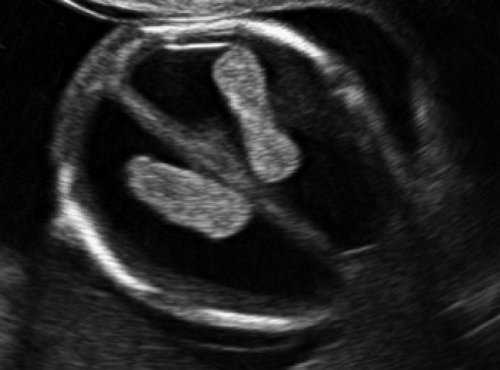

Рис. 7. Вентрикуломегалия у плода со spina bifida, беременность 12,4 недель.